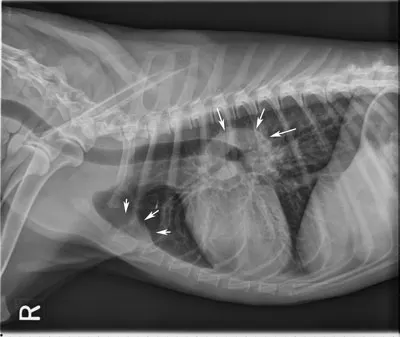

• Thoracic radiographs (Figure 3)

• Abdominal imaging (I typically perform abdominal radiographs or ultrasound only in cases with obvious peripheral lymphadenopathy if there is an unexpected     clinical sign referencing the abdomen, or if required for definitive diagnosis where infiltrative tissues are confined to the abdomen)